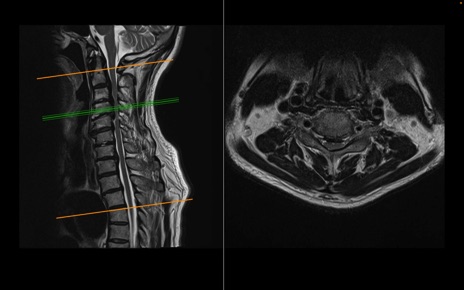

頚椎MRI

T2WI(横断像)

T2WI(矢状断像)